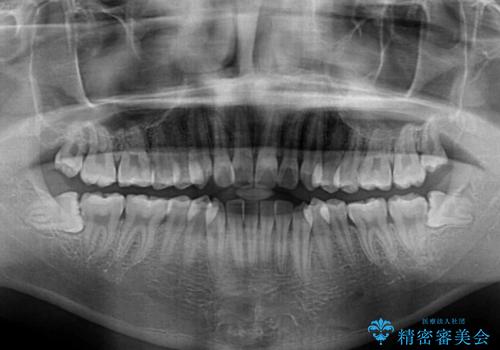

- 上下前歯のデコボコを気にして来院された患者様です。

インビザラインによる上下歯列の拡大と、IPR(歯と歯の間を削る)にるスペースの獲得により、前歯のデコボコと狭い歯列を改善することとしました。

比較的軽度な歯列不正であったため、治療期間はそれほど長くはならないと予想されました。

また、仕上がりの歯列にも若干の叢生が残ってしまいました。